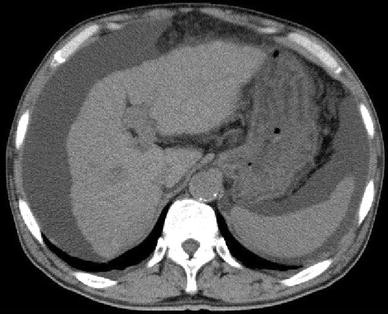

On plain abdominal computed tomography (Fig. 1), both the hepatic lobes were atrophic with a blunt margin and irregularity on the surface. A moderate volume of ascites retention was observed.

Plain abdominal computed tomography image. The hepatic lobes are atrophic with a blunt margin and irregularity on the surface. A moderate volume of ascites retention is also observed